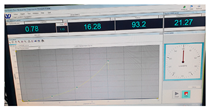

| Fracture force graphic |  |  |  |

| Fracture force graphic |  |  |  |

| Fracture force graphic |  |  |  |

| Fracture force graphic |  |  |  |

| Fracture force graphic |  |  |  |

| Fracture force graphic | N.A. | N.A. | N.A. |

| G8 | 7.67 | 0.04 | 1.60 | 52.29 | 1012.7 | 1355.4 | 0.23 |

| G12 | 11 | 0.10 | 1.9 | 71 | 1329.1 | 808.5 | 0.30 |

| G14 | 13 | 0.09 | 2.08 | 82.07 | 1458.1 | 1103.3 | 0.55 |

| G16 | 5.84 | 0.12 | 1.39 | 92.32 | 1607.6 | 890.1 | 0.38 |

| G14i5 | 30.9 | 0.15 | 3.21 | 83.25 | 1489.4 | 1642.7 | 0.50 |

| G14i10 | 33 | 0.20 | 3.32 | 80.73 | 1547.6 | 1289.6 | 0.52 |

| G14i15 | 39.2 | 0.28 | 3.62 | 71.5 | 1223.6 | 1863.7 | 0.67 |

| G14alc10 | 14.9 | 0.08 | 2.23 | 70.75 | 917.5 | 2162.3 | 0.38 |

| G14alc20 | 23 | 0.11 | 2.77 | 60.43 | 1054.4 | 1904.5 | 0.38 |

| G14s32:17.5 | 38.3 | 0.93 | 3.57 | 74.87 | 1025.6 | 1574.6 | 1.13 |

| G14s32:15 | 32.7 | 0.71 | 3.30 | 65.69 | 993.3 | 1414.6 | 2.01 |

| G14s32:12.5 | 35.45 | 0.71 | 3.44 | 64.75 | 1333.6 | 1336.2 | 2.16 |

| G14s32:10 | 27.1 | 0.75 | 3 | 50.85 | 1144.6 | 1314.8 | 2.28 |

| G14s32:7.5 | 35.15 | 0.67 | 3.42 | 49.9 | 1398.8 | 1397.4 | 1.81 |

| Pig liver (ex vivo) | 32.1 | 0.94 | 3.27 | 76.06 | 1131.5 | 176.1 | 1.26 |